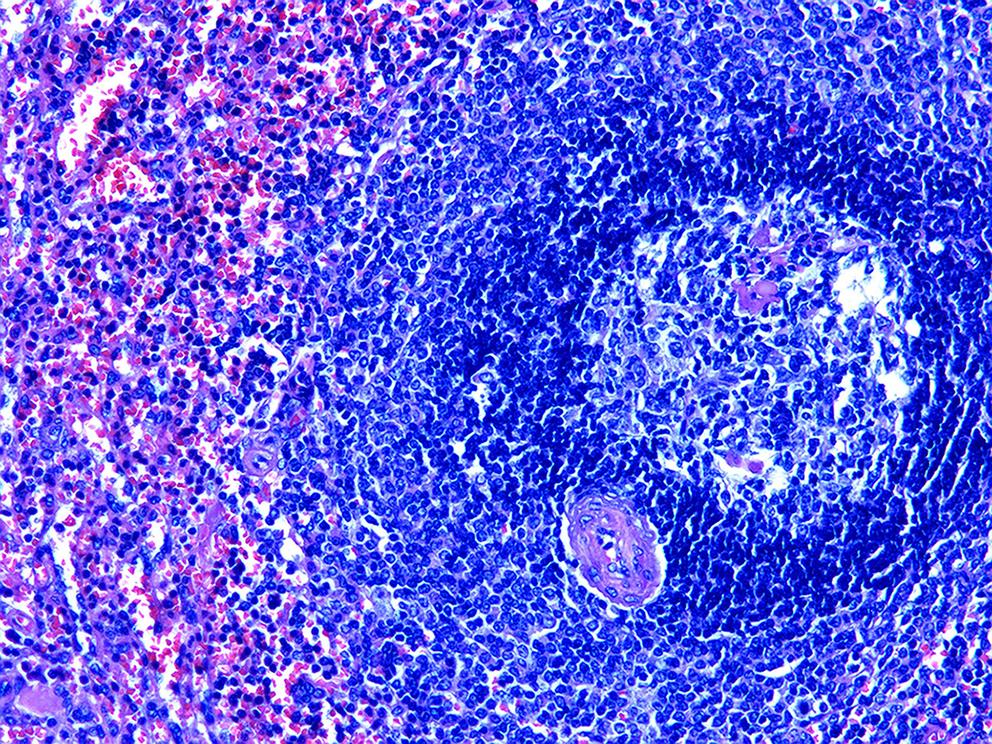

胰腺内副脾误诊2例报告

摘要(1364) HTML (331) PDF (1188KB)(157)

摘要:

副脾是指正常脾脏以外存在的,与主脾结构相似,有一定功能的脾脏组织,其中完全被胰腺包裹的胰腺内副脾(IPAS)发生率仅为2%,因其临床症状不典型,影像学特征与胰腺神经内分泌肿瘤、胰腺实性假乳头状瘤以及其他胰腺占位性病变较为相似,临床上容易误诊。本文报道了2例分别被误诊为胰腺神经内分泌肿瘤和胰腺实性假乳头状瘤的IPAS患者,并分析误诊原因,总结诊疗经验,以期提升临床对IPAS明确鉴别诊断的认识。